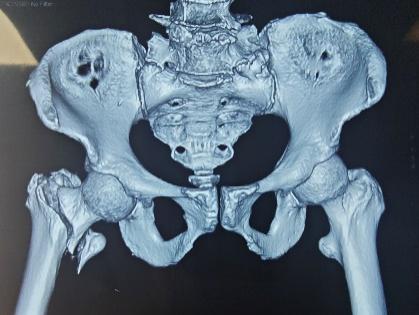

在王争刚主任医师主刀下,手术团队精准取出移位的内固定物,细致处理坏死骨组织,并在骨质缺损区域进行精确重建,最后植入人工髋关节假体。整台手术仅用时1小时,术中出血量少,假体安放位置理想,为患者后续的快速康复奠定了坚实基础。

术后X线片